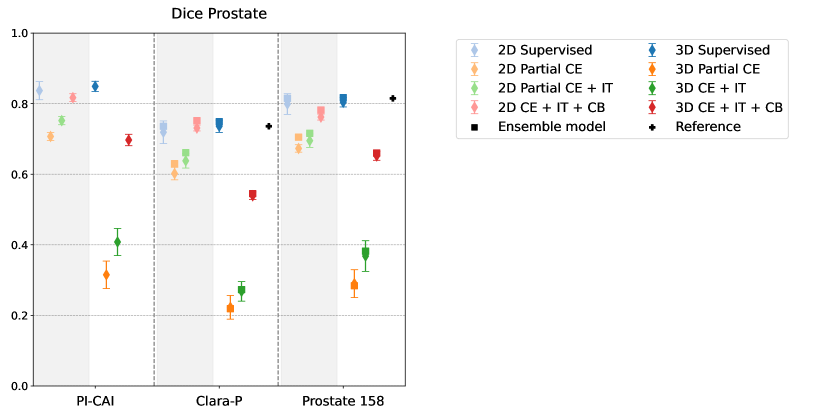

Appendix G Model results for prostate segmentation

Although not within the scope of this work, we provide hereunder a similar visualization than Figure 1 for the prostate segmentation Dice score. As suggested by the examples predictions maps shown in Figures 3 and 8, the regularization induced by the common bounds loss greatly improves the segmentation in the weakly supervised setup compared to models with partial cross-entropy (CE) or cross-entropy and image tag (CE+IT). Note that the bounds and were set roughly for the prostate class : in the 2D case, we used the ones that were set in [Duran et al.(2022)Duran, Dussert, and Lartizien], and in 3D case, we empirically set them based on the analysis of the distribution of prostate sizes.